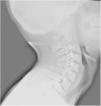

En la valoración, refiere dolor cervical y odinofagia. En la exploración se objetiva un hematoma cervical anterior. Se realiza una radiografía cervical para descartar lesiones de la vía aérea, identificando una lesión compatible con fractura de hioides (fig. 1). Se confirma el diagnóstico de fractura-luxación del asta mayor izquierda del hueso hioides mediante TC, descartando lesiones asociadas (figs. 2 y 3). Se decide tratamiento conservador con analgesia, dieta semiblanda y corticoterapia. Se realiza una laringoscopia que descarta complicaciones. Dada la buena evolución, se decide alta a las 24 h.